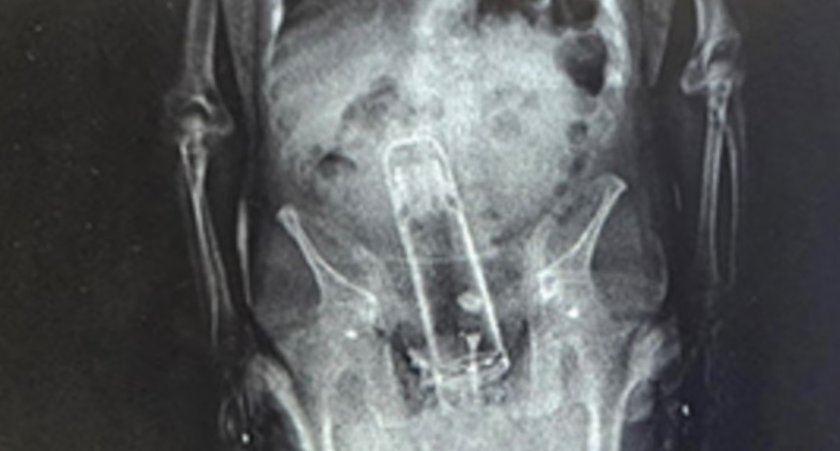

Американски пандизчия беше арестуван при опит да внесе зад решетките не наркотици, оръжие или дори мобилен телефон, а... еднолитров термос. За целта 51-годишният Уолтър Фримайър е заврял съда в ануса си, твърди шерифското бюро във Флорида.

Полицаите открили метамфетамини у мъжагата, но голямата изненада дошла при прегледа след ареста. Докторите установили огромно чуждо тяло в дупарата на нещастника.

Според полицията Фримайър е бил закаран в болница, а предметът е отстранен. Няма никакви данни защо, по дяволите, арестантът си е мушнал термоса отзад.